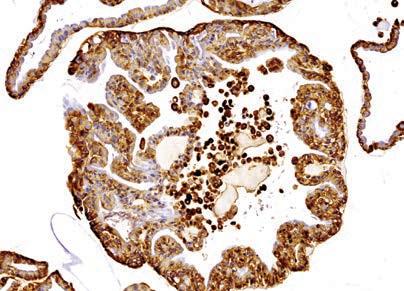

Hepatocellular Carcinoma and Chronic Hepatitis B: The GP’s Role.

Chronic hepatitis B (CHB) causes hepatocellular carcinoma (HCC)

CHB is the most common cause of HCC worldwide. For those living with CHB, the risk of developing HCC is up to 100 times higher than those who don’t. Liver cancer is the fastest growing cause of cancer death in Australia.

Between 20-25% of people with CHB die from complications of the disease, specifically cirrhosis and HCC. Globally that is one death every 44 seconds or about the time it takes to read this paragraph. With optimal monitoring and treatment, these deaths are largely preventable, and HCC can be detected early.

Overseas migrants and Aboriginal people are at highest risk of CHB and HCC

An estimated 220,000 Australians are living with CHB, with 10% in WA. Overseas migrants (61%) and Aboriginal and Torres Strait Islander people (11%) are the populations most affected, and also have the highest rates of HCC.

Antiviral medication is the best way to prevent HCC in CHB. When treatment is commenced at the right time, the risk of HCC is reduced by 30% in patients with cirrhosis and 80% in patients without.